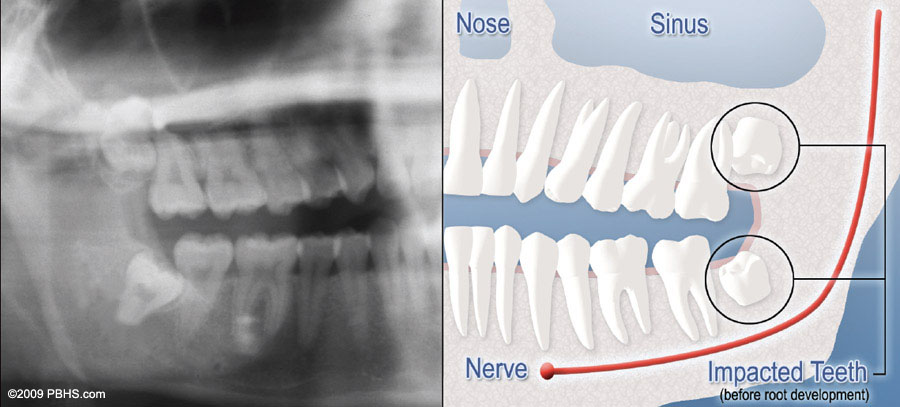

Although most people develop and grow 32 permanent adult teeth, many times their jaws are too small to accommodate the four wisdom teeth. When inadequate space prevents the teeth from erupting they are called impacted. This indicates their inability to erupt into the proper position for chewing and cleaning.

There is NO space for the tooth to erupt. It remains embedded in the jaw bone or if even partially visible requires complex surgical techniques for removal. The impacted wisdom tooth may also be in an unusual position and difficult to remove. This situation can also arise when the shape or size of the jaw bone and other facial structures make removal of this tooth significantly more complex.